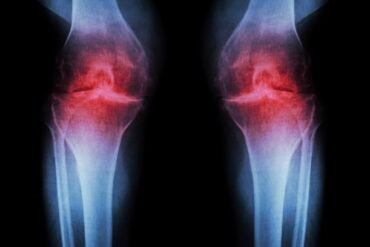

Introduction Rheumatoid Arthritis (RA) is a chronic autoimmune disorder that primarily affects the joints, causing pain, inflammation, and impaired mobility. While conventional treatments focus on symptom management, naturopathic approaches offer holistic strategies that address the underlying causes of RA and promote overall well-being. In this comprehensive article, we explore naturopathic treatments and therapies that can effectively alleviate RA symptoms, improve joint function, and enhance the quality of life for individuals living with this condition.

Rheumatoid Arthritis (RA) is a complex autoimmune disorder that affects millions worldwide. Understanding its underlying causes and recognizing the symptoms is crucial for effective management and timely intervention. In this section, we delve into the primary causes of RA and the common symptoms that individuals with this condition may experience.

- Swelling and Inflammation: Joints become swollen, tender, and warm due to inflammation.

- Joint Involvement: RA often affects joints symmetrically, such as both wrists or knees.